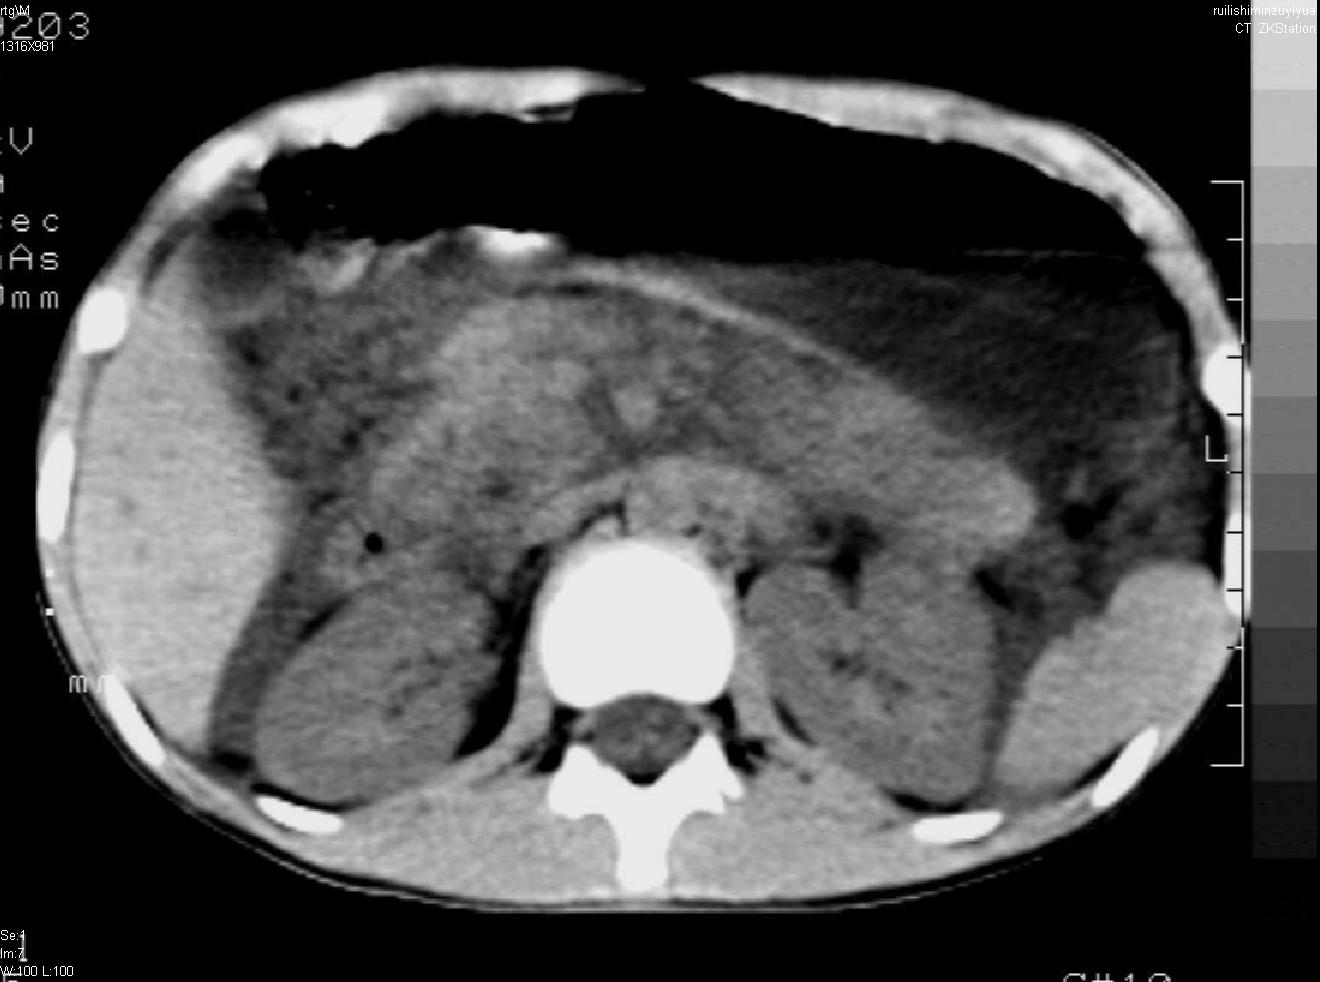

标题: PED0282:女,10岁,上腹疼痛2周 [打印本页]

标题: PED0282:女,10岁,上腹疼痛2周

b超:胆囊结石。疑坏死性胰腺炎

支持小儿急性坏死性胰腺炎。

支持急性胰腺炎。

支持急性胰腺炎并腹膜炎。

急性胰腺炎,腹腔积液